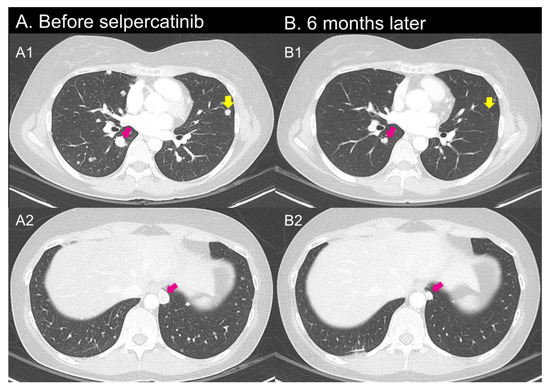

2.3. Case 3